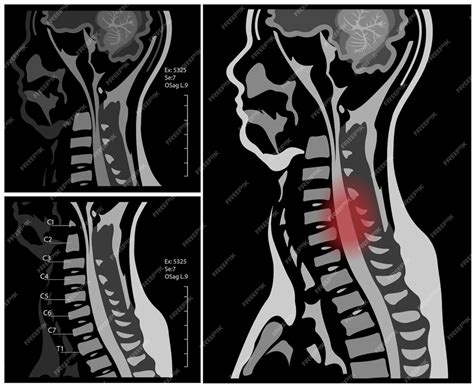

If you have been get continuing neck pain, radiate irritation into your arms, or unexplained numbness, your healthcare provider may urge an MRI Cervical Spine Without Contrast to inquire the fundamental campaign. This diagnostic imaging procedure is view the gold standard for project the soft tissues of the neck, include the spinal cord, intervertebral record, nerves, and surrounding ligaments. Unlike X-rays or CT scans, an MRI does not use ionize radiation, making it a safer and highly detailed option for assessing complex anatomical construction in the cervical region.

An MRI Cervical Spine Without Contrast utilizes powerful magnetic field and radio undulation to generate detailed, cross-sectional image of the seven vertebra located in your neck. The condition "without contrast" indicates that no contrast dye (gd) is inject into your bloodstream. This is typically the first-line tomography approach because it provides especial contrast between different case of soft tissue, allowing radiologist to descry abnormalities without the need for additional agent.

After the image are captured, a radiologist - a physician particularize in diagnostic imaging - will canvas the datum. They appear for signal changes, structural misalignment, and space-occupying lesion. The radiologist will generate a report detail their determination, which is then mail to your cite dr.. Your doctor will then review these results in the circumstance of your physical symptoms and medical chronicle.